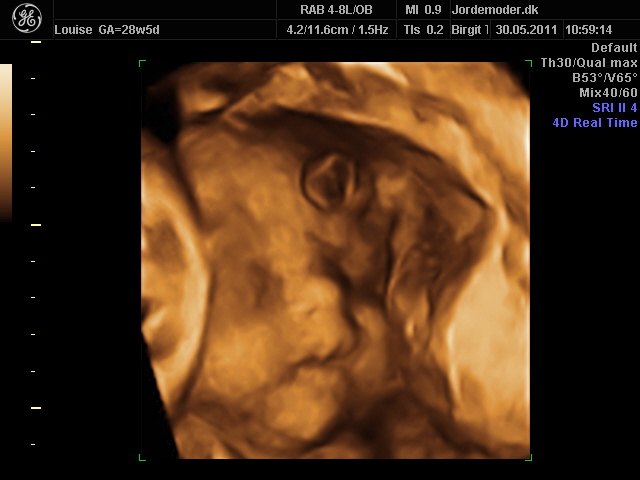

Så kom vi til 3d scanning igår. Lillepigen er slet ikke så stor som egen Jm kønnede hende HELDIGVIS! 1500 gram ca vejer hun nu, 28+6....

Hun har den fineste mund, jeg er helt misundelig på de smukker læber hun har.¨Ja hun er jo alt i alt bare dejlig, og jeg har ikke engang set hende sådan helt rigtig endnu.... Også har hun nogen gode runde kinder....

I skal ikke snydes for billeder af vores lille skønhed...